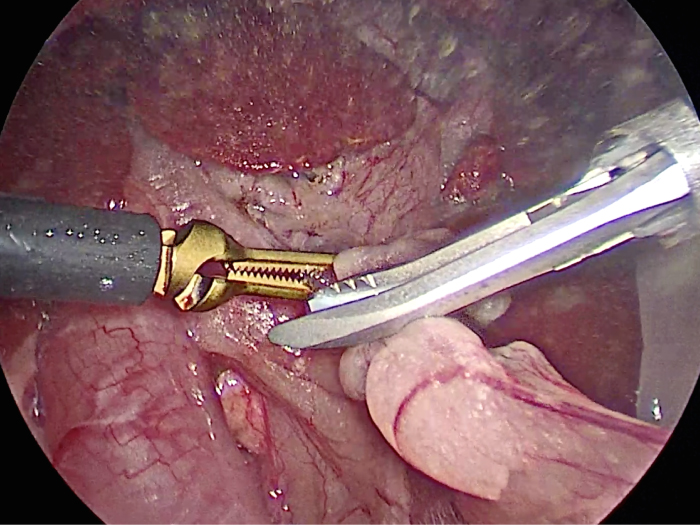

胆嚢の頸部に糸を通し動脈を確保しています。

総胆洗浄をして詰まりがないかまずは確認します。(右)

きれいに開通していました。鉗子が大きく感じますが体が小さいので大きく見えます。

胆嚢を少しずつ丁寧に肝臓から剥がしています。